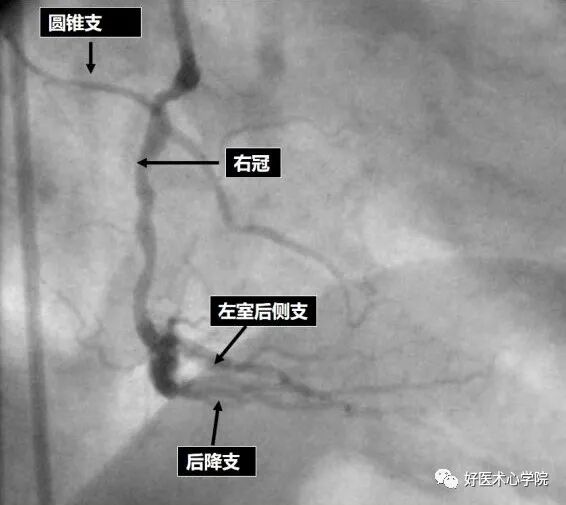

左前斜位:观察右冠全长,但难以看到远段分叉。

此时可以加足位可以观察。

△左前斜位下的右冠